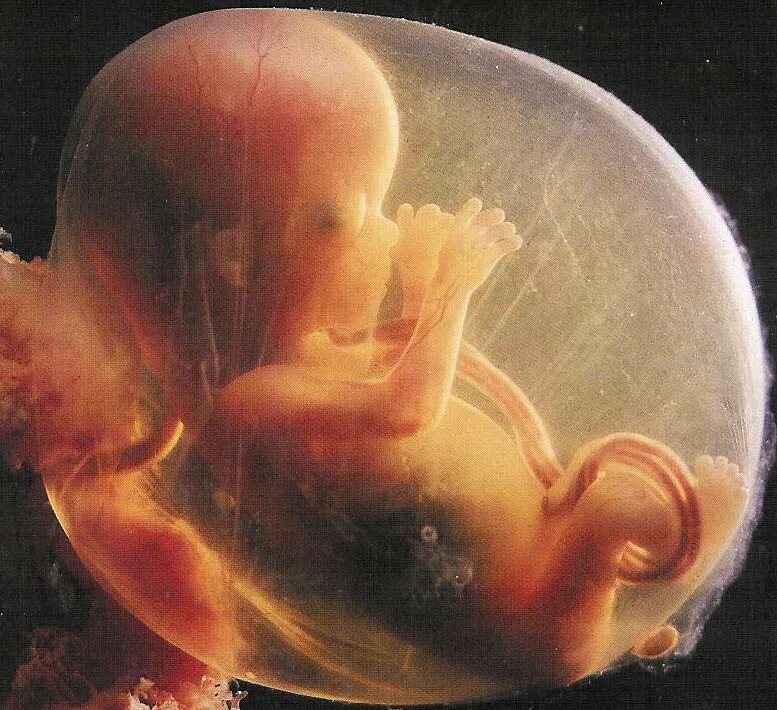

18 недель как выглядит малыш